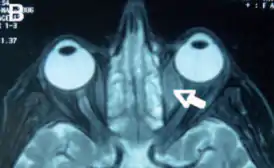

Орбитальная лимфома

Орбитальная лимфома является распространенным типом неходжкинской лимфомы, что происходит вблизи глаза или в глазе. Общие симптомы включают в себя снижение зрения и увеит. Орбитальная лимфома может быть диагностирована с помощью биопсии глаза и обычно лечится с помощью лучевой терапии или её комбинации с химиотерапией.

Основные видимые симптомы глазной лимфомы включают экзофтальм и видимую массу в глазе. Другие симптомы связаны с масс-эффектом.